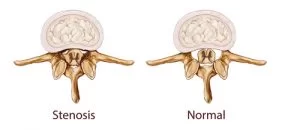

Τι είναι η σπονδυλική στένωση;

Η σπονδυλική στένωση είναι μια στένωση του καναλιού της σπονδυλικής στήλης, η οποία μπορεί να ασκήσει πίεση στα νευρικά στοιχεία της σπονδυλικής στήλης (Εικόνα 2). Η σπονδυλική στένωση εμφανίζεται συχνότερα στην οσφύ (μέση) και στον αυχένα.